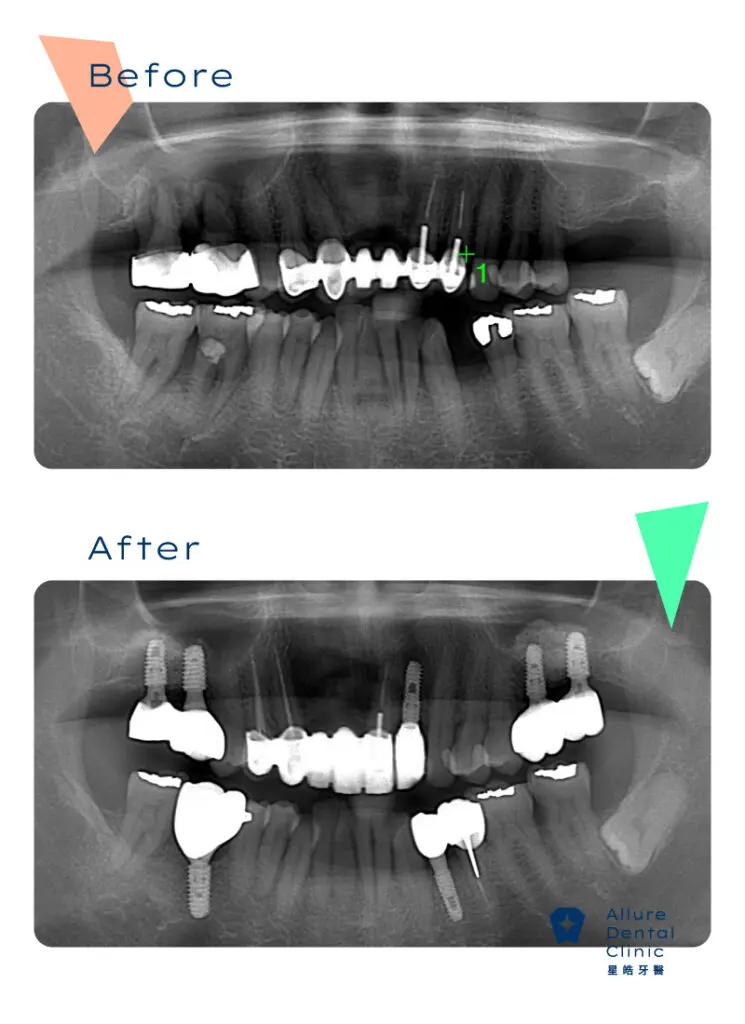

全口重建案例2

主治醫師:副院長 林禹書 醫師